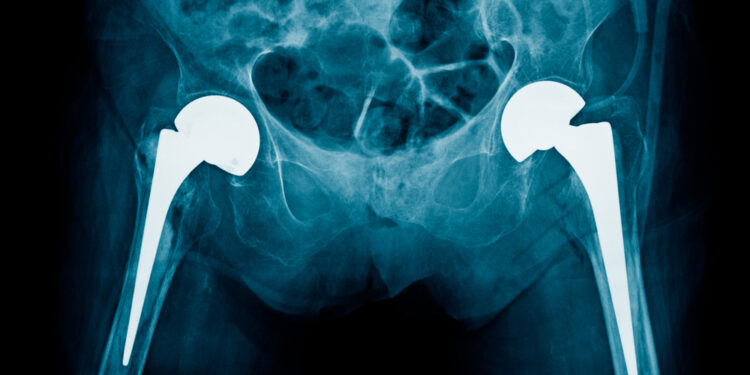

Patyrus klubo sąnario traumą, gydytojas pirmiausia įvertins pažeistos kojos padėtį ir bendrą būklę. Tiksliai diagnozei dažniausiai reikalingi vaizdiniai tyrimai – rentgenograma arba kompiuterinė tomografija, kurios leidžia nustatyti ne tik išnirusio kaulo padėtį, bet ir atmesti galimus lūžius ar kitus pažeidimus. Tik atlikus išsamų ištyrimą galima saugiai atkurti sąnario vietą.

Dirbtinio sąnario priežiūra

Kai sąnarys pakeistas implantu, išnirimo atveju kartais prireikia implanto taisymo ar keitimo. Gydytojas rekomenduos geriausią sprendimą pagal situaciją ir paciento būklę.